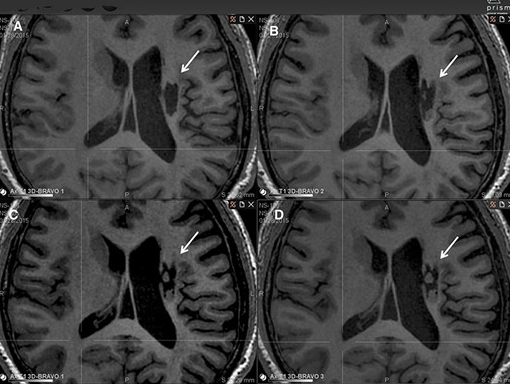

影像學(xué)檢查:在 6 個(gè)月的隨訪中,所有 9 名受試者均觀察到新組織,源自腦軟化梗塞腔。該腔內(nèi)組織外觀具有以下特征:短期活力(術(shù)后第一次 MRI 與基線相比的組織外觀)—9 例中有 9 例;生長(術(shù)后至少兩次 MRI 中新組織增加)—6 例中有 6 例;穩(wěn)定(術(shù)后至少兩次 MRI 中新組織沒有變化;即生長平臺(tái)期,最長為 24 個(gè)月)—6 例中有 5 例;無法獲得 24 個(gè)月后的長期活力。

(A)基線時(shí),(B) 6 個(gè)月隨訪時(shí),(C) 12 個(gè)月隨訪時(shí),(D) 24 個(gè)月隨訪時(shí)。